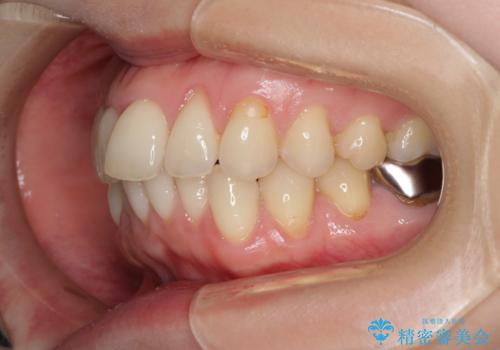

出産をしながら歯列を整える インビザラインによる矯正治療

- 上下の前歯のデコボコを気にして来院された患者様です。

妊娠中であり、途中通院が難しくなる可能性があることから、インビザラインによる矯正治療を行うこととしました。

上下顎歯列全体の後方移動とIPR(歯と歯の間を削る)によってデコボコが解消するように設計しました。